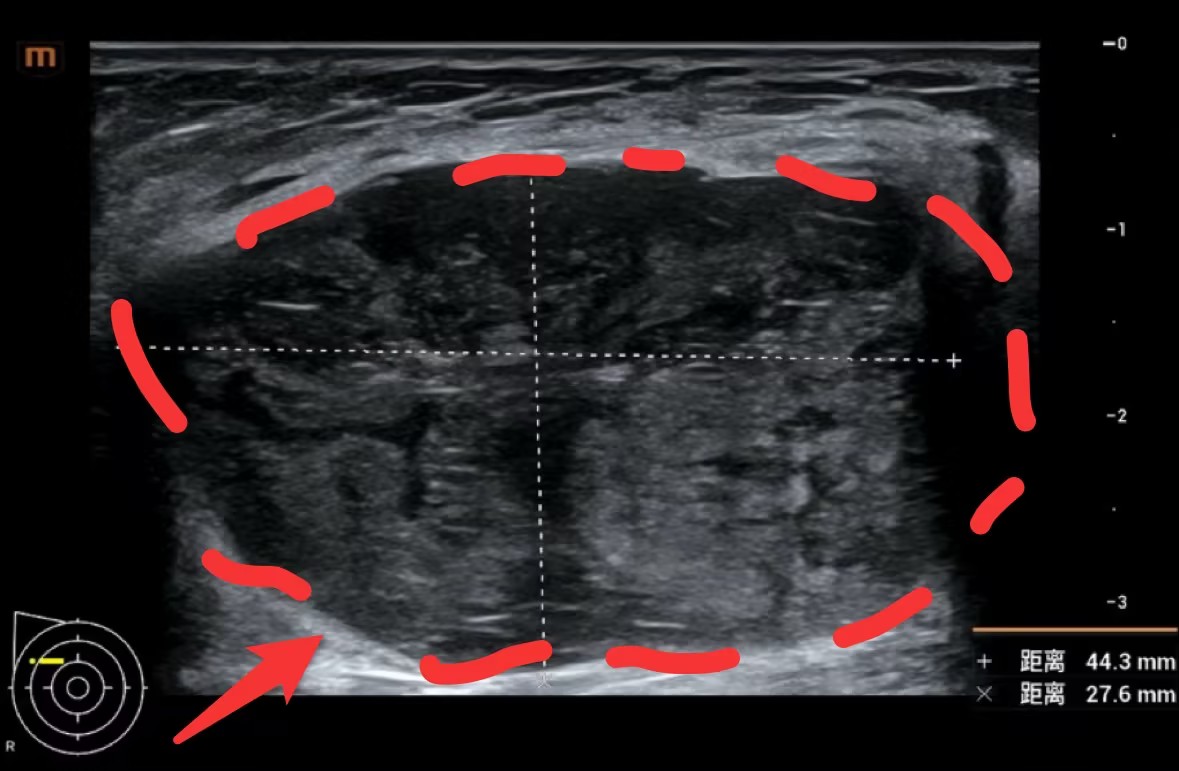

乳腺彩超及钼靶下巨大肿物,完整切除测量约5cm